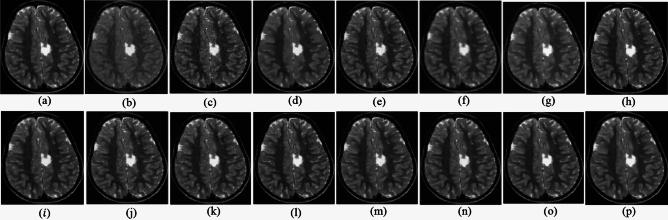

Medical imaging systems such as computed tomography (CT) and magnetic resonance imaging (MRI) are vital tools in clinical diagnosis and treatment planning. However, these modalities are inherently susceptible to Gaussian noise introduced during image acquisition, leading to degraded image quality and impaired visualization of critical anatomical structures. Effective denoising is therefore essential to enhance diagnostic accuracy while preserving fine details such as tissue textures and structural boundaries. This study proposes a robust and efficient denoising framework specifically designed for CT and MRI images corrupted by Gaussian noise. The method integrates a cluster-wise principal component analysis (PCA) thresholding approach guided by the Marchenko-Pastur (MP) law from random matrix theory and a non-local means algorithm. Noise level estimation is achieved globally by analysing the statistical distribution of eigenvalues from noisy image patch matrices and leveraging the MP law to accurately determine the Gaussian noise variance. An adaptive clustering technique is employed to group similar patches based on underlying features such as textures and edges and enables localized denoising operations tailored to heterogeneous image regions. Within each cluster denoising is performed in two stages where initially hard thresholding based on the MP law is applied to the singular values in the SVD domain to obtain a low-rank approximation that preserves essential image content while removing noise-dominated components. Residual noise in the low-rank matrix is then further suppressed through a coefficient-wise linear minimum mean square error LMMSE estimator in the PCA transform domain. Finally, a non-local means algorithm refines the denoised image by computing weighted averages of pixel intensities and prioritizing neighbourhood similarity over spatial proximity to effectively preserve edges and textures while reducing Gaussian noise. Experimental evaluations on CT and MRI datasets demonstrate that the proposed method achieves superior denoising performance while maintaining high structural similarity and perceptual quality compared to existing state-of-the-art approaches. The method demonstrates adaptability noise reduction capability and preservation of anatomical detail that make it well suited for precision critical medical imaging applications.

计算机断层扫描(CT)和磁共振成像(MRI)等医学成像系统是临床诊断和治疗规划中的重要工具。然而,这些模态在图像采集过程中固有地容易受到高斯噪声的影响,导致图像质量下降以及关键解剖结构的可视化受损。因此,有效的去噪对于提高诊断准确性同时保留诸如组织纹理和结构边界等精细细节至关重要。本研究提出了一种强大且高效的去噪框架,专门针对受高斯噪声破坏的CT和MRI图像设计。该方法集成了一种由随机矩阵理论中的马尔琴科 - 帕斯图尔(MP)定律引导的聚类主成分分析(PCA)阈值处理方法和一种非局部均值算法。通过分析噪声图像块矩阵的特征值统计分布并利用MP定律来准确确定高斯噪声方差,实现全局噪声水平估计。采用自适应聚类技术根据纹理和边缘等潜在特征对相似块进行分组,并针对异质图像区域进行局部去噪操作。在每个聚类中,去噪分两个阶段进行,首先在奇异值分解(SVD)域中基于MP定律应用硬阈值处理奇异值,以获得保留基本图像内容同时去除噪声主导成分的低秩近似。然后在PCA变换域中通过系数线性最小均方误差(LMMSE)估计器进一步抑制低秩矩阵中的残余噪声。最后,非局部均值算法通过计算像素强度的加权平均值并优先考虑邻域相似性而非空间邻近性来细化去噪图像,从而在减少高斯噪声的同时有效保留边缘和纹理。对CT和MRI数据集的实验评估表明,与现有的最先进方法相比,所提出的方法在保持高结构相似性和感知质量的同时实现了卓越的去噪性能。该方法展示了适应性降噪能力和解剖细节保留能力,使其非常适合精密关键的医学成像应用。